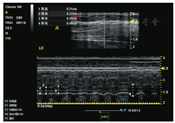

膈肌厚度的测量通常选择肋间入路。检查时,受检者取半卧位,上身倾斜30°,检查者将B型线性高频探头(10~15 MHz)置于受检者右腋前线/腋中线第8~11肋间[14,16],垂直于皮肤,图像可见三层平行的高低相间的回声层,其中上下两层高回声区为胸膜层、腹膜层,中间混杂回声区为膈肌层,两条高回声区之间的距离(不包含两条高回声本身的厚度)即为膈肌厚度。膈肌厚度的超声图像见图1。膈肌厚度变化率=(最大吸气末膈肌厚度-平静呼气末膈肌厚度)/平静呼气末膈肌厚度。据报道,健康一般人群膈肌厚度为(1.7±0.2) mm[17],肺容量从残气量增至肺总量时,膈肌厚度平均可增加54%[14]。

图中白色标注1:呼气末膈肌厚度,2:平静吸气末膈肌厚度;3:用力吸气末膈肌厚度;4:电刺激吸气末膈肌厚度。